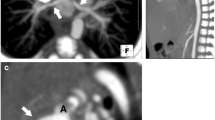

A Jatene arterial switch requires serial imaging for quantitative evaluation of the function of the ventricles, ischemic complications (due to coronary artery translocation) and evaluation of the outflow tracts for obstruction and insufficiency (Fig. 18.23) [26]. In patients in whom the presence of coronary ischemia is suspected, conventional catheter coronary angiography is probably the imaging modality of choice.

Cardiac CTA images in the axial (a) and oblique sagittal (b) planes in a patient of Jatene arterial switch and Le compte manoeuvre show the main pulmonary artery (MPA) anterior to the neoaorta. There is significant ostial stenosis of the left pulmonary artery (white solid arrow) and short segment mild narrowing of the ascending aorta (*)

The pulmonary arteries need assessment for central and peripheral stenosis related to inadequate growth. Dilatation of neoaorta is invariable, and despite neoaortic root dilatation, haemodynamically significant aortic valve regurgitation is uncommon. Infrequently, a neoaorta aneurysm bulges into the pulmonary bifurcation during systole. The anatomic and functional significance of such obstructions can be more accurately assessed with MR imaging.